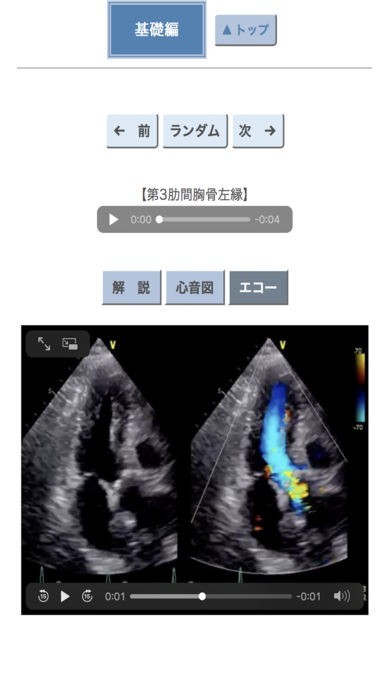

ポケット心音のスクリーンショット